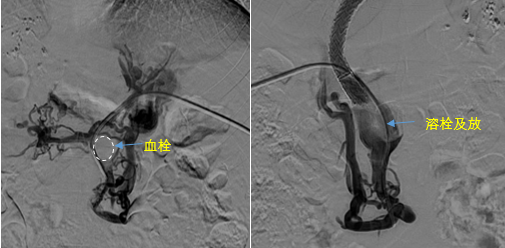

• 血栓攔路,如何破局——罕見巨大門靜脈血栓TIPS手術(shù)實(shí)錄

血栓攔路,如何破局——罕見巨大門靜脈血栓TIPS手術(shù)實(shí)錄

日前,西安國際醫(yī)學(xué)中心醫(yī)院消化病醫(yī)院為一位罕見巨大門靜脈血栓患者行TIPS手術(shù)。將患者體內(nèi)的“定時(shí)炸彈”拆除。9月份的一天,李女士晚飯后發(fā)覺惡心,嘔吐出鮮紅色的血塊,隨即又出現(xiàn)了黑便。在醫(yī)院檢查發(fā)現(xiàn)是食管胃底靜脈曲張破裂出血?!?/p>